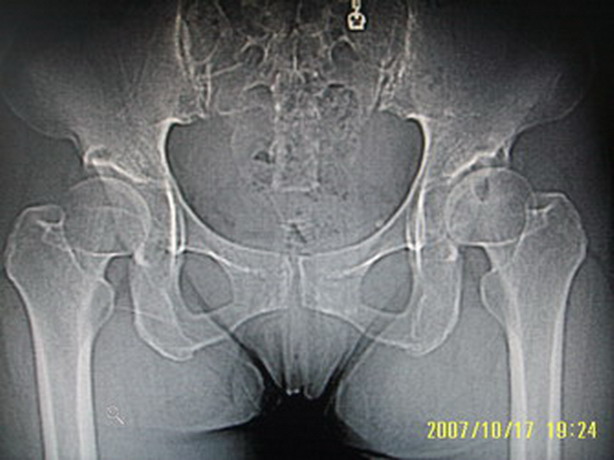

标题: CT10352:女,45岁,股骨头病变,如何诊断?

股骨头病变,如何诊断?

患者女,45岁,左髋部行走疼痛一年,无外伤史,无感染史。x片示囊状骨透亮区

两侧髋臼结构发育不良伴退行性改变.不除外色素沉着绒毛结节性滑膜炎.

两侧髋臼结构发育不良伴退行性改变

支持成人髋臼发育不良继发髋关节退行性变

髋关节发育不良,左髋关节退变,左髋关节邻关节囊肿

双侧股骨头形态都欠规整,外形欠光滑,尤以左侧明显,考虑双侧髋臼发育不良并退行性变